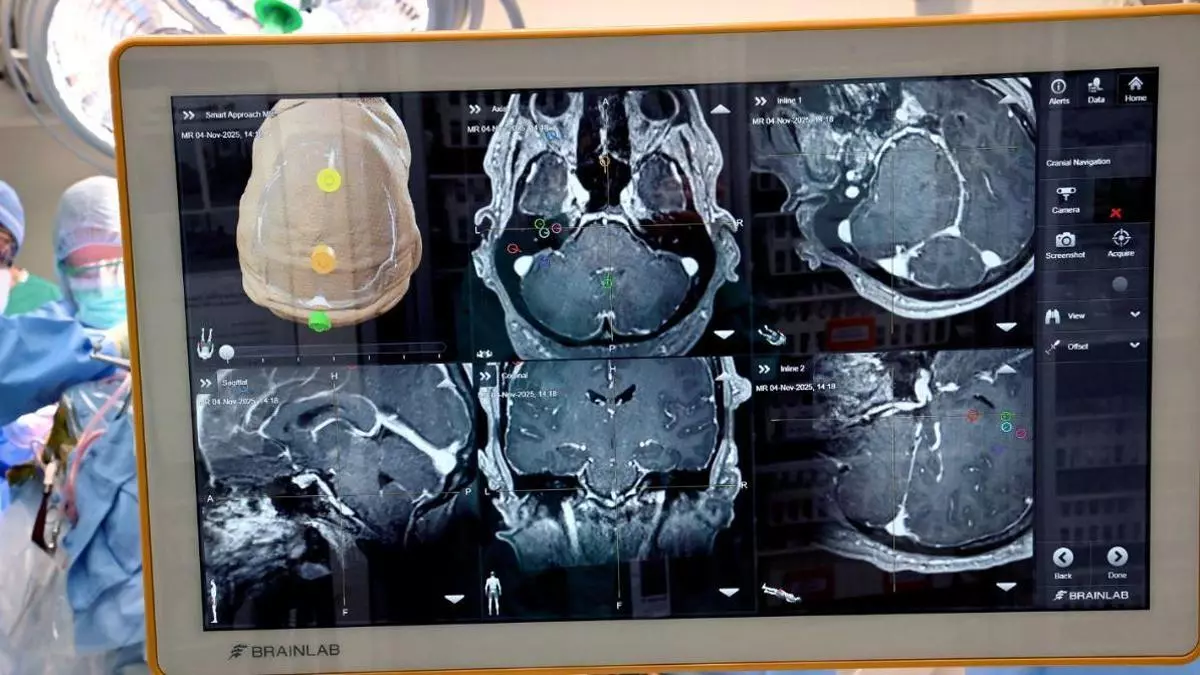

La operación abre una nueva vía para interpretar señales cerebrales en regiones vinculadas a funciones más complejas. / Crédito: Universidad de Colorado Anschutz.

Investigadores de la Universidad de Colorado Anschutz y UCHealth en Colorado, Estados Unidos, han realizado una cirugía que podría modificar el futuro de la neurotecnología: por primera vez, lograron implantar una interfaz cerebro-ordenador (BCI, por sus siglas en inglés) en zonas superiores del cerebro, y no en las regiones motoras primarias donde se habían concentrado la mayoría de los procedimientos previos.

Patterson se convirtió en el primer ser humano en recibir este tipo de implante en una zona cortical de mayor nivel funcional. La cirugía dejó instalados tres puertos en la parte superior de su cabeza, capaces de comunicar la actividad cerebral con ordenadores externos.

La innovación principal tiene que ver con el lugar donde se colocó el implante: la mayoría de las BCI se han enfocado hasta ahora en regiones puramente motoras, mientras que esta intervención apunta a áreas más altas del cerebro, vinculadas con procesos más complejos de planificación, decisión y conversión del pensamiento en acción. Según una nota de prensa, eso podría ofrecer una relación más natural y completa entre el cerebro, el movimiento y las sensaciones.